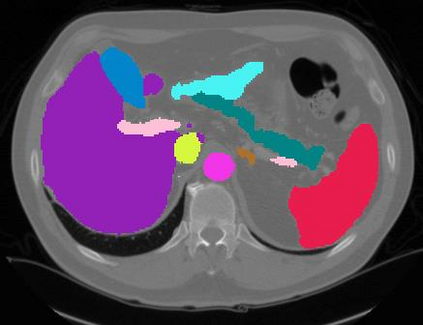

Vision transformers, with their ability to more efficiently model long-range context, have demonstrated impressive accuracy gains in several computer vision and medical image analysis tasks including segmentation. However, such methods need large labeled datasets for training, which is hard to obtain for medical image analysis. Self-supervised learning (SSL) has demonstrated success in medical image segmentation using convolutional networks. In this work, we developed a \underline{s}elf-distillation learning with \underline{m}asked \underline{i}mage modeling method to perform SSL for vision \underline{t}ransformers (SMIT) applied to 3D multi-organ segmentation from CT and MRI. Our contribution is a dense pixel-wise regression within masked patches called masked image prediction, which we combined with masked patch token distillation as pretext task to pre-train vision transformers. We show our approach is more accurate and requires fewer fine tuning datasets than other pretext tasks. Unlike prior medical image methods, which typically used image sets arising from disease sites and imaging modalities corresponding to the target tasks, we used 3,643 CT scans (602,708 images) arising from head and neck, lung, and kidney cancers as well as COVID-19 for pre-training and applied it to abdominal organs segmentation from MRI pancreatic cancer patients as well as publicly available 13 different abdominal organs segmentation from CT. Our method showed clear accuracy improvement (average DSC of 0.875 from MRI and 0.878 from CT) with reduced requirement for fine-tuning datasets over commonly used pretext tasks. Extensive comparisons against multiple current SSL methods were done. Code will be made available upon acceptance for publication.